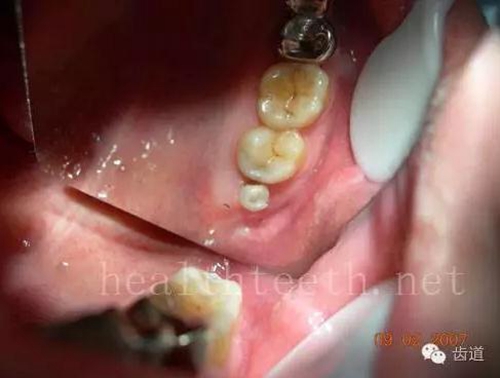

42.jpg

43.jpg

手術(shù)中切斷、完整拔出,未損傷上頜竇